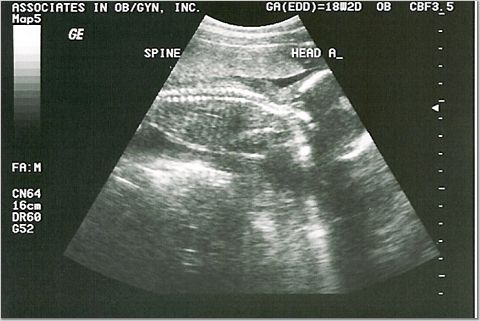

18 weeks - 7 & 8 ounces

We were supposed to find out the sexes, but they were too active for the tech to see!

Baby A and Baby B Spine